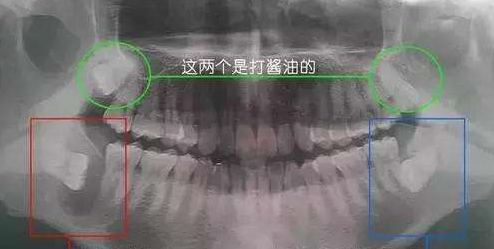

因为是为了更好的知道你的口腔情况,包括智齿周围情况和了解智齿结构。要知道每个人的口腔环境是不同的,自然智齿的生长形态也是千变万化的,牙根结构不尽相同。

现实的情况有可能是融合成一个根,也可能是八爪根。不同牙根不同位置及方向,只有通过拍片来确认。这样才能让牙医更好的,同时也是更有把握的帮你把牙齿拔好。

此外,有一小部分人的智齿会生长在下颌神经周围,如果冒昧的去拔智齿,可能存在一定的风险。医生基本上也不大愿意为了几百块去帮你拔离下颌神经线附近的智齿,毕竟一不小心,碰到神经,就摊上大事了。